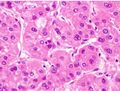

Macroscopically, liver cancer appears as a nodular or infiltrative tumor. The nodular type may be solitary (large mass) or multiple (when developed as a complication of cirrhosis). Tumor nodules are round to oval, gray or green (if the tumor produces bile), well circumscribed but not encapsulated. The diffuse type is poorly circumscribed and infiltrates the portal veins, or the hepatic veins (rarely).[16]

Microscopically, the four architectural and cytological types (patterns) of hepatocellular carcinoma are: fibrolamellar, pseudoglandular (adenoid), pleomorphic (giant cell), and clear cell. In well-differentiated forms, tumor cells resemble hepatocytes, form trabeculae, cords, and nests, and may contain bile pigment in the cytoplasm. In poorly differentiated forms, malignant epithelial cells are discohesive, pleomorphic, anaplastic, and giant. The tumor has a scant stroma and central necrosis because of the poor vascularization.[39] A fifth form – lymphoepithelioma like hepatocellular carcinoma – has also been described.[40][41]